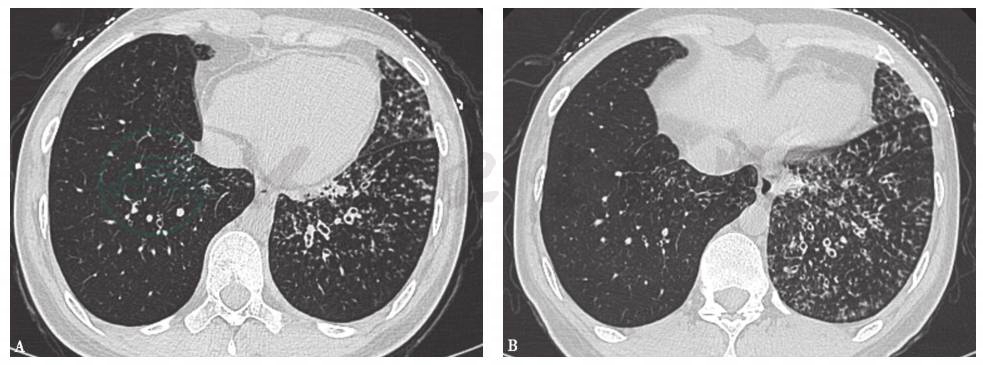

10天前胸部CT见双肺呈随机分布的弥漫性粟粒样小结节影(图2)。

图2 10天前胸部CT表现